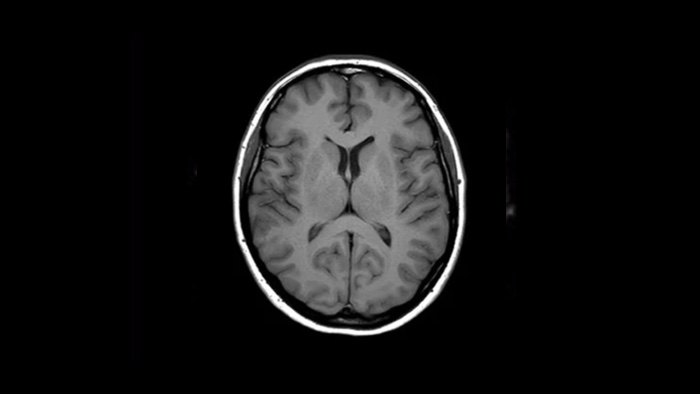

Ahora puede tenerlo todo con Ingenia Ambition. Ofrece la oportunidad de mejorar sus imágenes de resonancia magnética en todos los niveles.

Confianza diagnóstica Ofrece una resolución espacial hasta un 60% más alta en el mismo tiempo de escaneo. 4

Ahora puede tenerlo todo con Ingenia Ambition. Ofrece la oportunidad de mejorar sus imágenes de RM en todos los niveles.

Confianza diagnóstica Amplíe su capacidad de obtener imágenes excelentes en todas las áreas clínicas. Vea cómo se benefician sus compañeros.

Un salto en la confianza de la resonancia magnética pediátrica en Altona Children's Hospital.